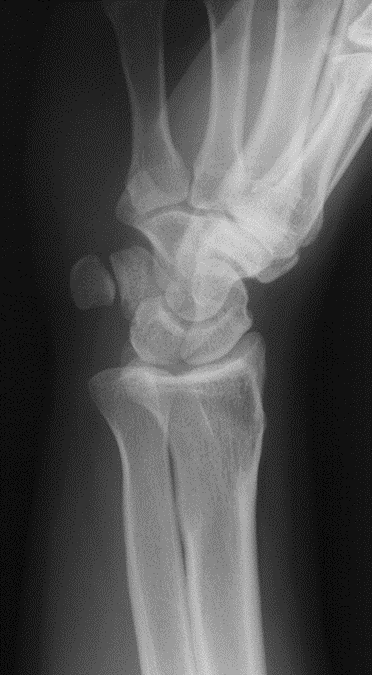

Colles Fracture

Distal radius fracture with fragment displaced posteriorly; often from fall on outstretched hand.

Routine Projections of the Wrist (4)

Lateral

Posteroanterior (PA)

45° Semi-pronated Oblique

45° Semi-supinated Oblique

What projection was performed to produce this image? What is the structure best demonstrated?

Lateral Wrist

Lunate